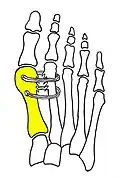

Syndesmosis procedure addresses specifically the two fundamental problems of metatarsus primus varus deformity that gives rise to the bunion deformity. They are leaning and instability of the first metatarsal bone . Syndesmosis procedure uprights the leaning first metatarsal bone with strong binding sutures between it and the second metatarsal bone (Fig. 2) and then also stabilizes it uniquely by creating a fibrous connecting bridge between these two bones (Fig. 3, 4). First metatarsal bone can be readily realigned because by definition of the metatarsus primus varus deformity its first metatarsal is abnormally loose and mobile.